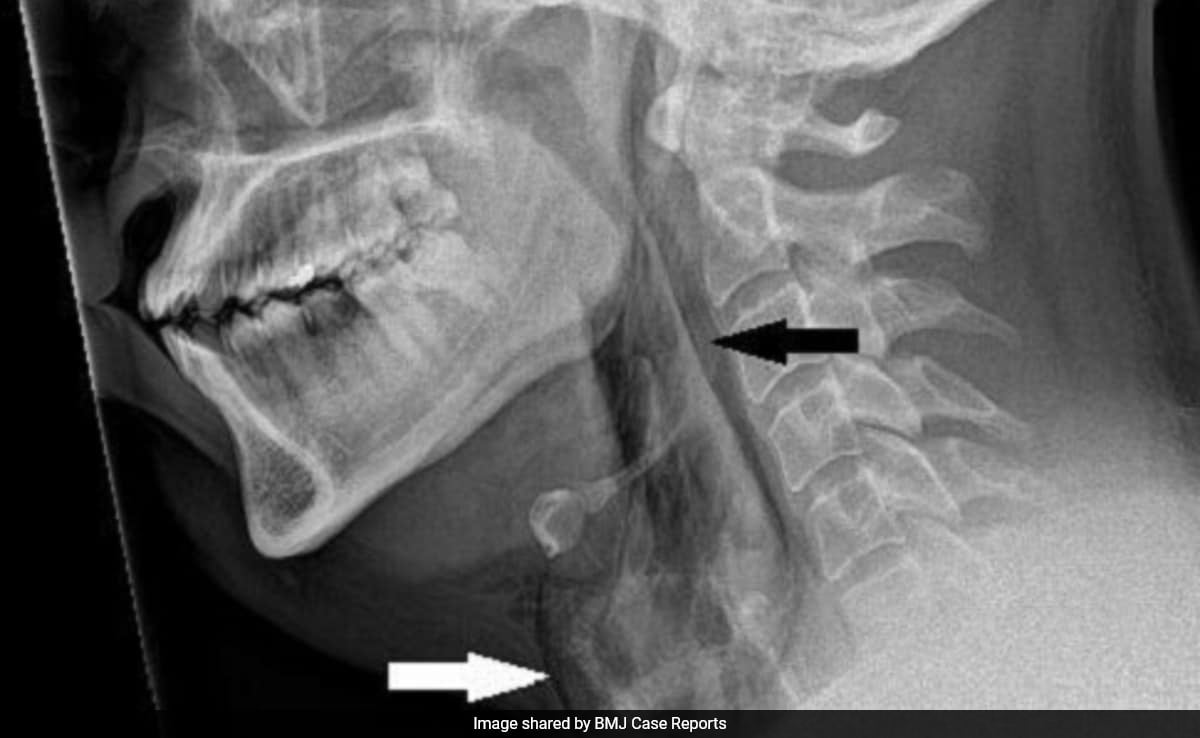

A 34-year-old man in Mexico suffered severe abdominal pain seconds after drinking a smoky cocktail infused with liquid nitrogen. He was found to have a ruptured stomach with pneumoperitoneum and underwent laparoscopic repair using tissue from his abdomen, recovering and being discharged three days later. The report highlights the dangers of consuming liquid nitrogen in beverages, which can rapidly expand as it warms, and notes that safety hinges on allowing the nitrogen to vaporize completely; the Leidenfrost effect may have helped shield tissue from cold burns.